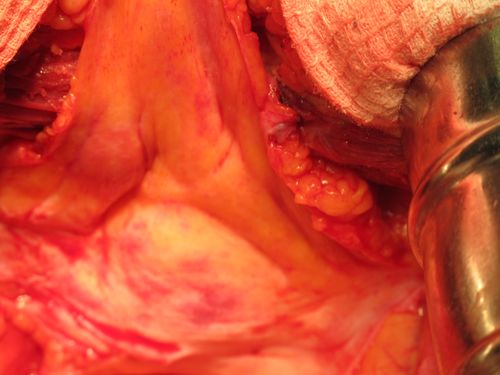

Лучевой цистит с исходом в микроцистис (цистпростатэктомия)